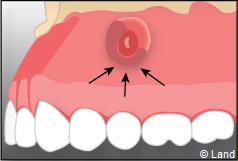

Une anesthésie et une incision semi lunaire sont réalisées et le lambeau de gencive est récliné.

Il faut localiser le bout de la racine de la dent atteinte, procéder au décollement de la lésion avec une curette à bords tranchants, couper et enlever la partie de racine infectée.